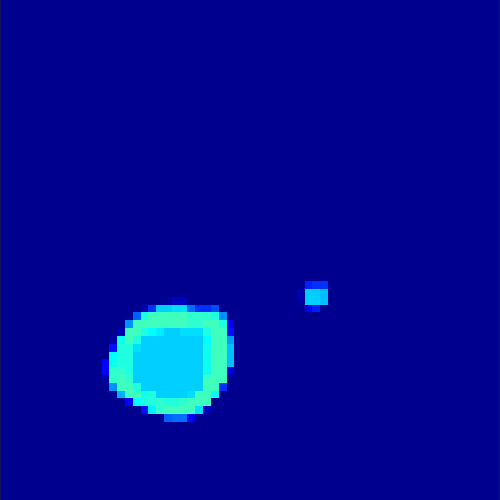

5.2 Monte Carlo Simulation

In order to test the behaviour of the proposed method in a more realistic, random-based test case, we performed a Monte Carlo simulation for dynamic SPECT imaging. First, we created a simple image phantom consisting of an outer and two inner circles which represents the structure of the region of interest (see figure 8(a)). Within those regions we assumed concentration curves over a time period of 90 time steps as displayed in figure 8(b). Based on the tracer intensity in an image frame at each time step, we created a variable number of random decay events (where the number is proportional to the average concentration in one pixel in the whole image frame per time step) with a probability proportional to the concentration in every subregion. They are detected by a virtual double head gamma camera rotating around the patient by 46 degrees per time step, which consists of 374 detector bins. Every simulated decay event is projected onto the scanner and counted by the corresponding detector bin.

In two different tests we fixed the number of events counted by the detector equal to (resp. ) times the average concentration in one pixel. The resulting sinogram images of the accumulated counts in each bin are shown in figure 9.

Based on the sinogram data we applied the proposed algorithm in order to reconstruct the original image sequence. The results for both test cases are shown in figure 10.

As one can see, the method is able to reconstruct the regions properly, even in case of a low count number. Within a number of iterations (average of 100 outer and 10000 inner iterations), the algorithm presents a reasonable reconstruction of the region of interest and the corresponding regional tracer concentration curves. Here, the parameters were not optimized as in the case of the synthesized data sets in the previous section, but kept fixed as , and . With futher optimized parameter values one could possibly provide even better results.